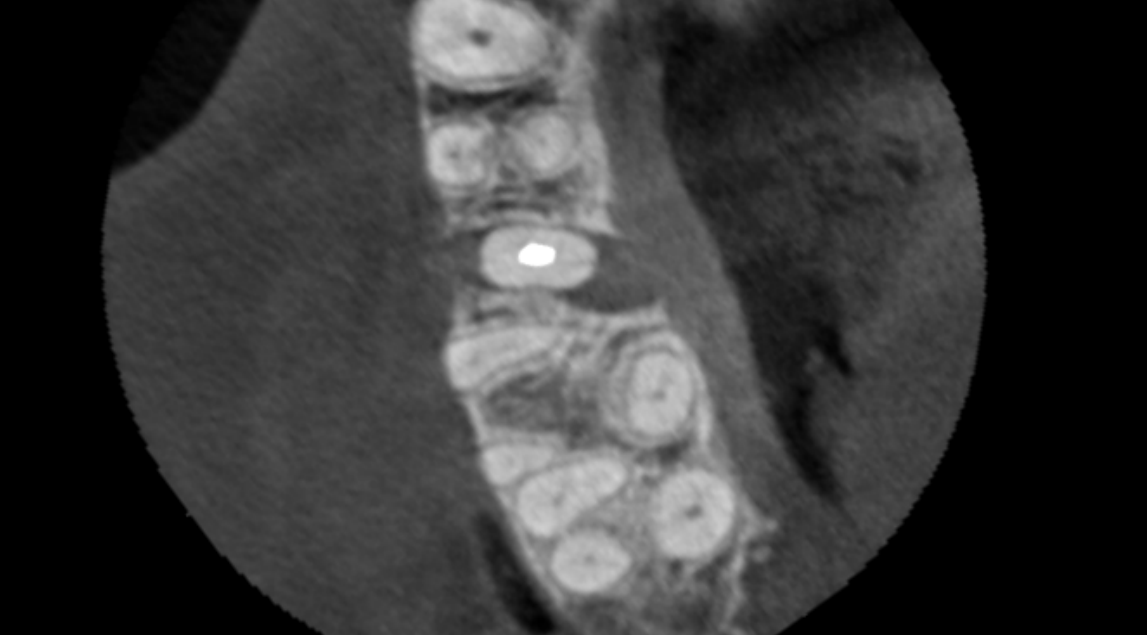

Case 24 – Endodontics

Transillumination after trauma